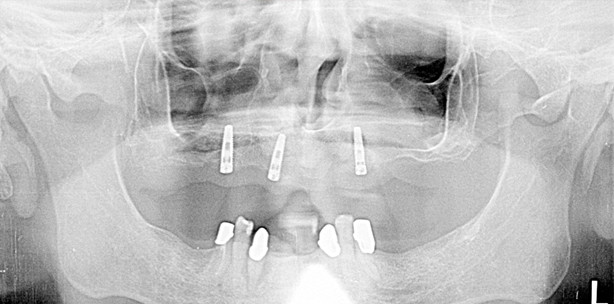

Im folgenden Fall war aufgrund der schlechten Ausgangssituation eine aufwendige Gebiss-Restauration nötig. Um die Zeit bis zur Eingliederung...

Im Folgenden wird die Anfertigung einer implantatgetragenen, bedingt herausnehmbaren Hybridbrücke beschrieben. Durch eine direkt mit Implantaten...

Im Folgenden wird die Anfertigung einer implantatgetragenen, bedingt herausnehmbaren Hybridbrücke...